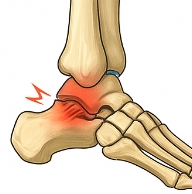

발목 접질렀을때 발생하는 원인

발목 접질렀을때 가장 흔한 원인은 발목 염좌입니다.

발목 접질렀을때 나타나는 주요 증상

발목 접질렀을때 다음과 같은 증상이 나타납니다.

- 통증: 발목 주변에 날카로운 통증이 즉시 발생.

- 붓기: 발목이 붓고 열감이 동반될 수 있습니다.

- 멍(피하출혈): 혈관이 손상되면 피부에 멍이 들 수 있습니다.

- 움직임 제한: 발목 접질렀을때 걷기 어렵거나 체중 부하 시 통증이 심해집니다.

이러한 증상은 발목 접질렀을때 손상의 정도에 따라 달라집니다.